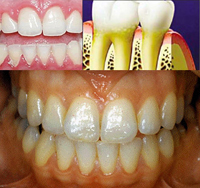

- Đừng để vôi răng gây viêm nướu,

- Đừng để nha chu qua giai có túi nướu (Pockets)

- Đừng để bệnh nha chu tiến triển sang đoạn 3 (tiêu xương ổ răng là răng bị lung lay) sẽ khó hồi phục.

• Tóm lại vũ khí để chống lại bệnh nha chu chính là bàn chải răng và chỉ tơ nha khoa (dental floss).